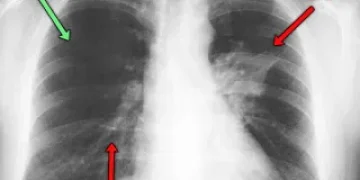

Рентгенография является важным инструментом в диагностике туберкулёза, так как позволяет визуализировать изменения в легких, характерные для этого заболевания. На рентгеновских снимках можно выявить различные формы туберкулёзной инфекции, включая инфильтративную, кавернозную и фиброзно-кавернозную. Важно правильно интерпретировать рентгенологические данные, так как различные виды патологий требуют различного подхода к лечению. Являясь медицинским специалистом, я утверждаю, что точная диагностика на этом этапе критически важна для начала адекватной терапии.

При анализе рентгенограмм следует учитывать как наличие, так и характер изменений: наличие узелков, затемнений, а также состояние плевры. Я обращаю внимание на то, что иногда рентгенологические проявления могут быть нечеткими, особенно на ранних стадиях заболевания, что требует комплексного подхода к диагностике, включая дополнительные методы исследования, такие как КТ легких или микробиологические тесты. Это помогает исключить возможные диагностические ошибки и установить правильный диагноз.

На рентгеновском снимке, если наблюдаются инфильтрат, каверна, жидкость в плевральном пространстве, цирроз или фиброз, это говорит о наличии заболевания лёгких — туберкулёза. Эти изменения существенно искажают легочный рисунок, уменьшая воздушность и задерживая рентгеновские лучи. В результате на снимке появляются тени, которые и указывают на наличие заболевания. Очаги туберкулёза отличаются по размеру и плотности, их классифицируют на крупные, средние и мелкие, а также плотные и менее плотные средние очаги.

Каждый размер имеет свои параметры: мелкие — до двух миллиметров, средние — до шести, крупные — до десяти миллиметров в диаметре. Очаги свыше десяти миллиметров называют туберкулемами или инфильтратами.

При милиарном туберкулёзе проявляются мелкие очаги. Крупные и средние очаги характерны для очагового, хронического, фиброзно-кавернозного и подострого туберкулёза. Очаги бывают свежими и старыми; свежие имеют меньшую плотность по сравнению со старыми. На снимке они четко видны и выглядят с размытыми границами.